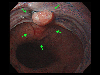

A case of IIc+IIa type early gastric cancer which invaded the esophagus.

Endoscopy